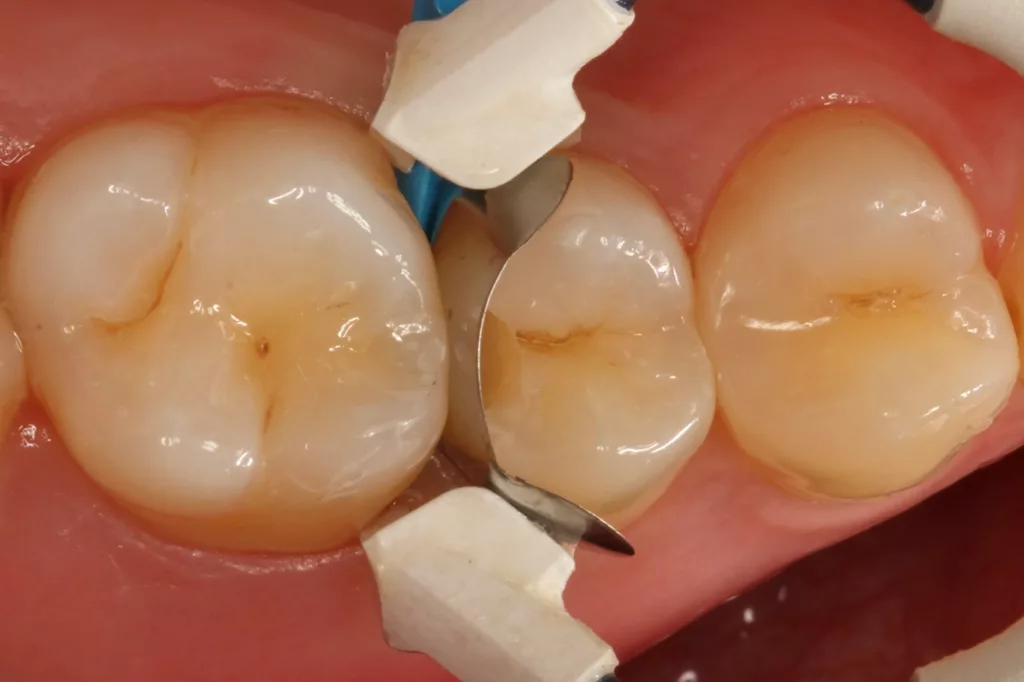

Fall 4: Versorgung von zwei benachbarten Approximalläsionen

Dass mit sehr dünnen Matrizenfolien auch zwei benachbarte Kavitäten gleichzeitig versorgt werden können, zeigt der Fall des 19-jährigen Patienten an den Zähnen 24 und 25. Die zeitgleiche Versorgung zweier benachbarter Kavitäten hat den Vorteil des ökonomischeren Arbeitens und der Reduktion einer Kontamination der zweiten Kavität mit dem Adhäsiv, bei dessen Verblasen in der als erste versorgten Kavität: Da es beim Matrizenwechsel nahezu immer zu einer Blutung oder sonstigen Kontamination kommt, muss eine erneute Reinigung bzw. Nachpräparation der zweiten Kavität vorgenommen werden. Ein ledigliches Ausspülen vor einer adhäsiven Versiegelung der Kavität dürfte ineffizient sein, da sich die Phosphorsäurekonditionierung der Schmelzränder durch die Verklebung der Oberfläche mit dem verblasenen Adhäsiv aus der erstversorgten Kavität kaum suffizient gestalten lassen dürfte.

Es müssten die Klebeflächen somit sekundär noch einmal angefrischt werden, was wiederum aufgrund der Enge in dem minimalinvasiven Kavitätenbereich einen erneuten und nicht ganz so einfachen Arbeitsschritt darstellt. Aus diesem Grunde ist die zeitgleiche Versorgung derartiger Approximalläsionen kontaminationstechnisch einfacher zu bewerkstelligen und somit vorzuziehen – vorausgesetzt der Approximalkontakt ist ausreichend stark. Dies wurde in dem vorliegenden Fall durch die Verwendung zweier sehr dünner (0,03 mm) Teilmatrizenfolien (QuickmatFLEX Titan, Polydentia, Schweiz, Abb. 20 und 21) sichergestellt. Die hervorragende Separationskraft des verwendeten NiTin-Spannringes garantiert eine ausreichende Kontaktstärke (Abb. 22).

Das Restaurationsprozedere folgte den vorangegangenen Fällen. Die Polymerisation von Adhäsiv (G2 Universal) und des Bulkflow-Komposites (Visalys Bulk Flow) erfolgte hingegen separat und nicht mit einer gemeinsamen Abdeckung beider Kavitäten mit dem 10 mm Lichtleiter der Elipar Deep Cure, um den Schattenwurf der beiden Teilmatrizen zu minimieren. Die Nachpolymerisation nach Abnahme beider Matrizen erfolgte hingegen nur einmal für beide Kavitäten: einmal von okklusal zentral und mittig auf beide, gerade neu aufgebaute Randleisten und einmal von approximal/bukkal. Das klinische Endergebnis überzeugte erneut funktional und ästhetisch. Die Abbildung 23 zeigt die klinische Kontrolle nach sechs Monaten: Es sind weder Randverfärbungen noch Desintegration erkennbar, die Ästhetik ist ebenso unverändert.